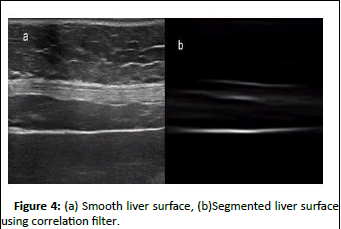

Figure 4(b) shows the result of segmentation of original image shown in Figure 4(a). Although a small extra part of abdominal wall is also detected along with liver surface but this can be efficiently removed by post processing.

Figure 4: (a) Smooth liver surface, (b)Segmented liver surface using correlation filter.